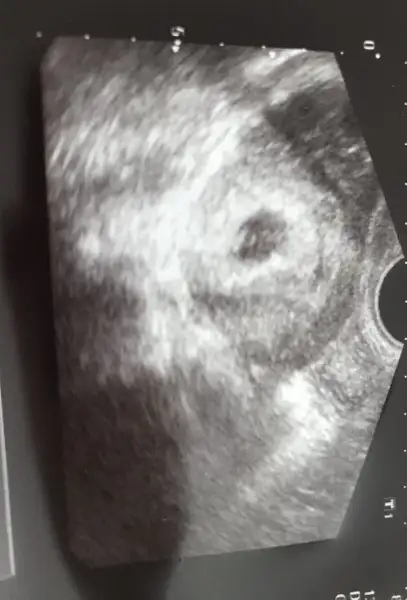

Kızlar sizin bu kese teorisine göre benimki yuvarlak mı olmuş oluyor baksanıza :halay:

Eklentiler

• IMG_0889.webp

IMG_0889.webp

10,9 KB · Görüntüleme: 63

Bana çin takvimi erkek diyor ama kesem yuvarlak